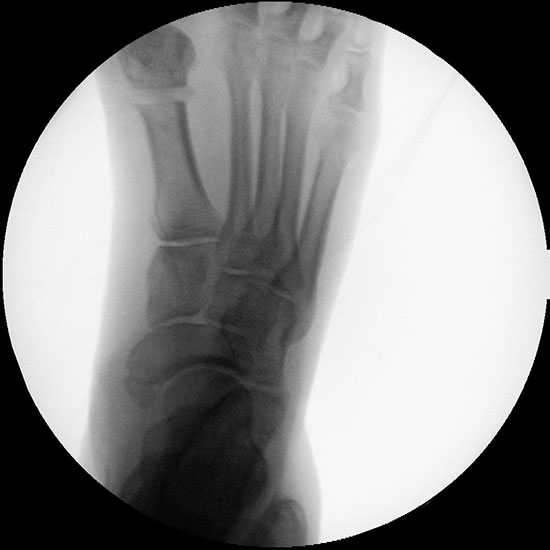

Präoperatives Röntgenbild Fuß d.p. mit eingezeichneten Winkeln. A) Intermetatarsalwinkel, B) Hallux valgus Winkel, C) Interphalangeal-Winkel.

Abbildung 2

• Operationsplanung anhand der Röntgenaufnahmen unter Beachtung wichtiger radiologischer Landmarks wie Intermetatarsalwinkel, Hallux valgus – Winkel, distaler Gelenkflächenwinkel (Distal Metatarsal Articular Angulation - DMAA), Metatarsaleindex und Sesambeinposition (Abb. 2).